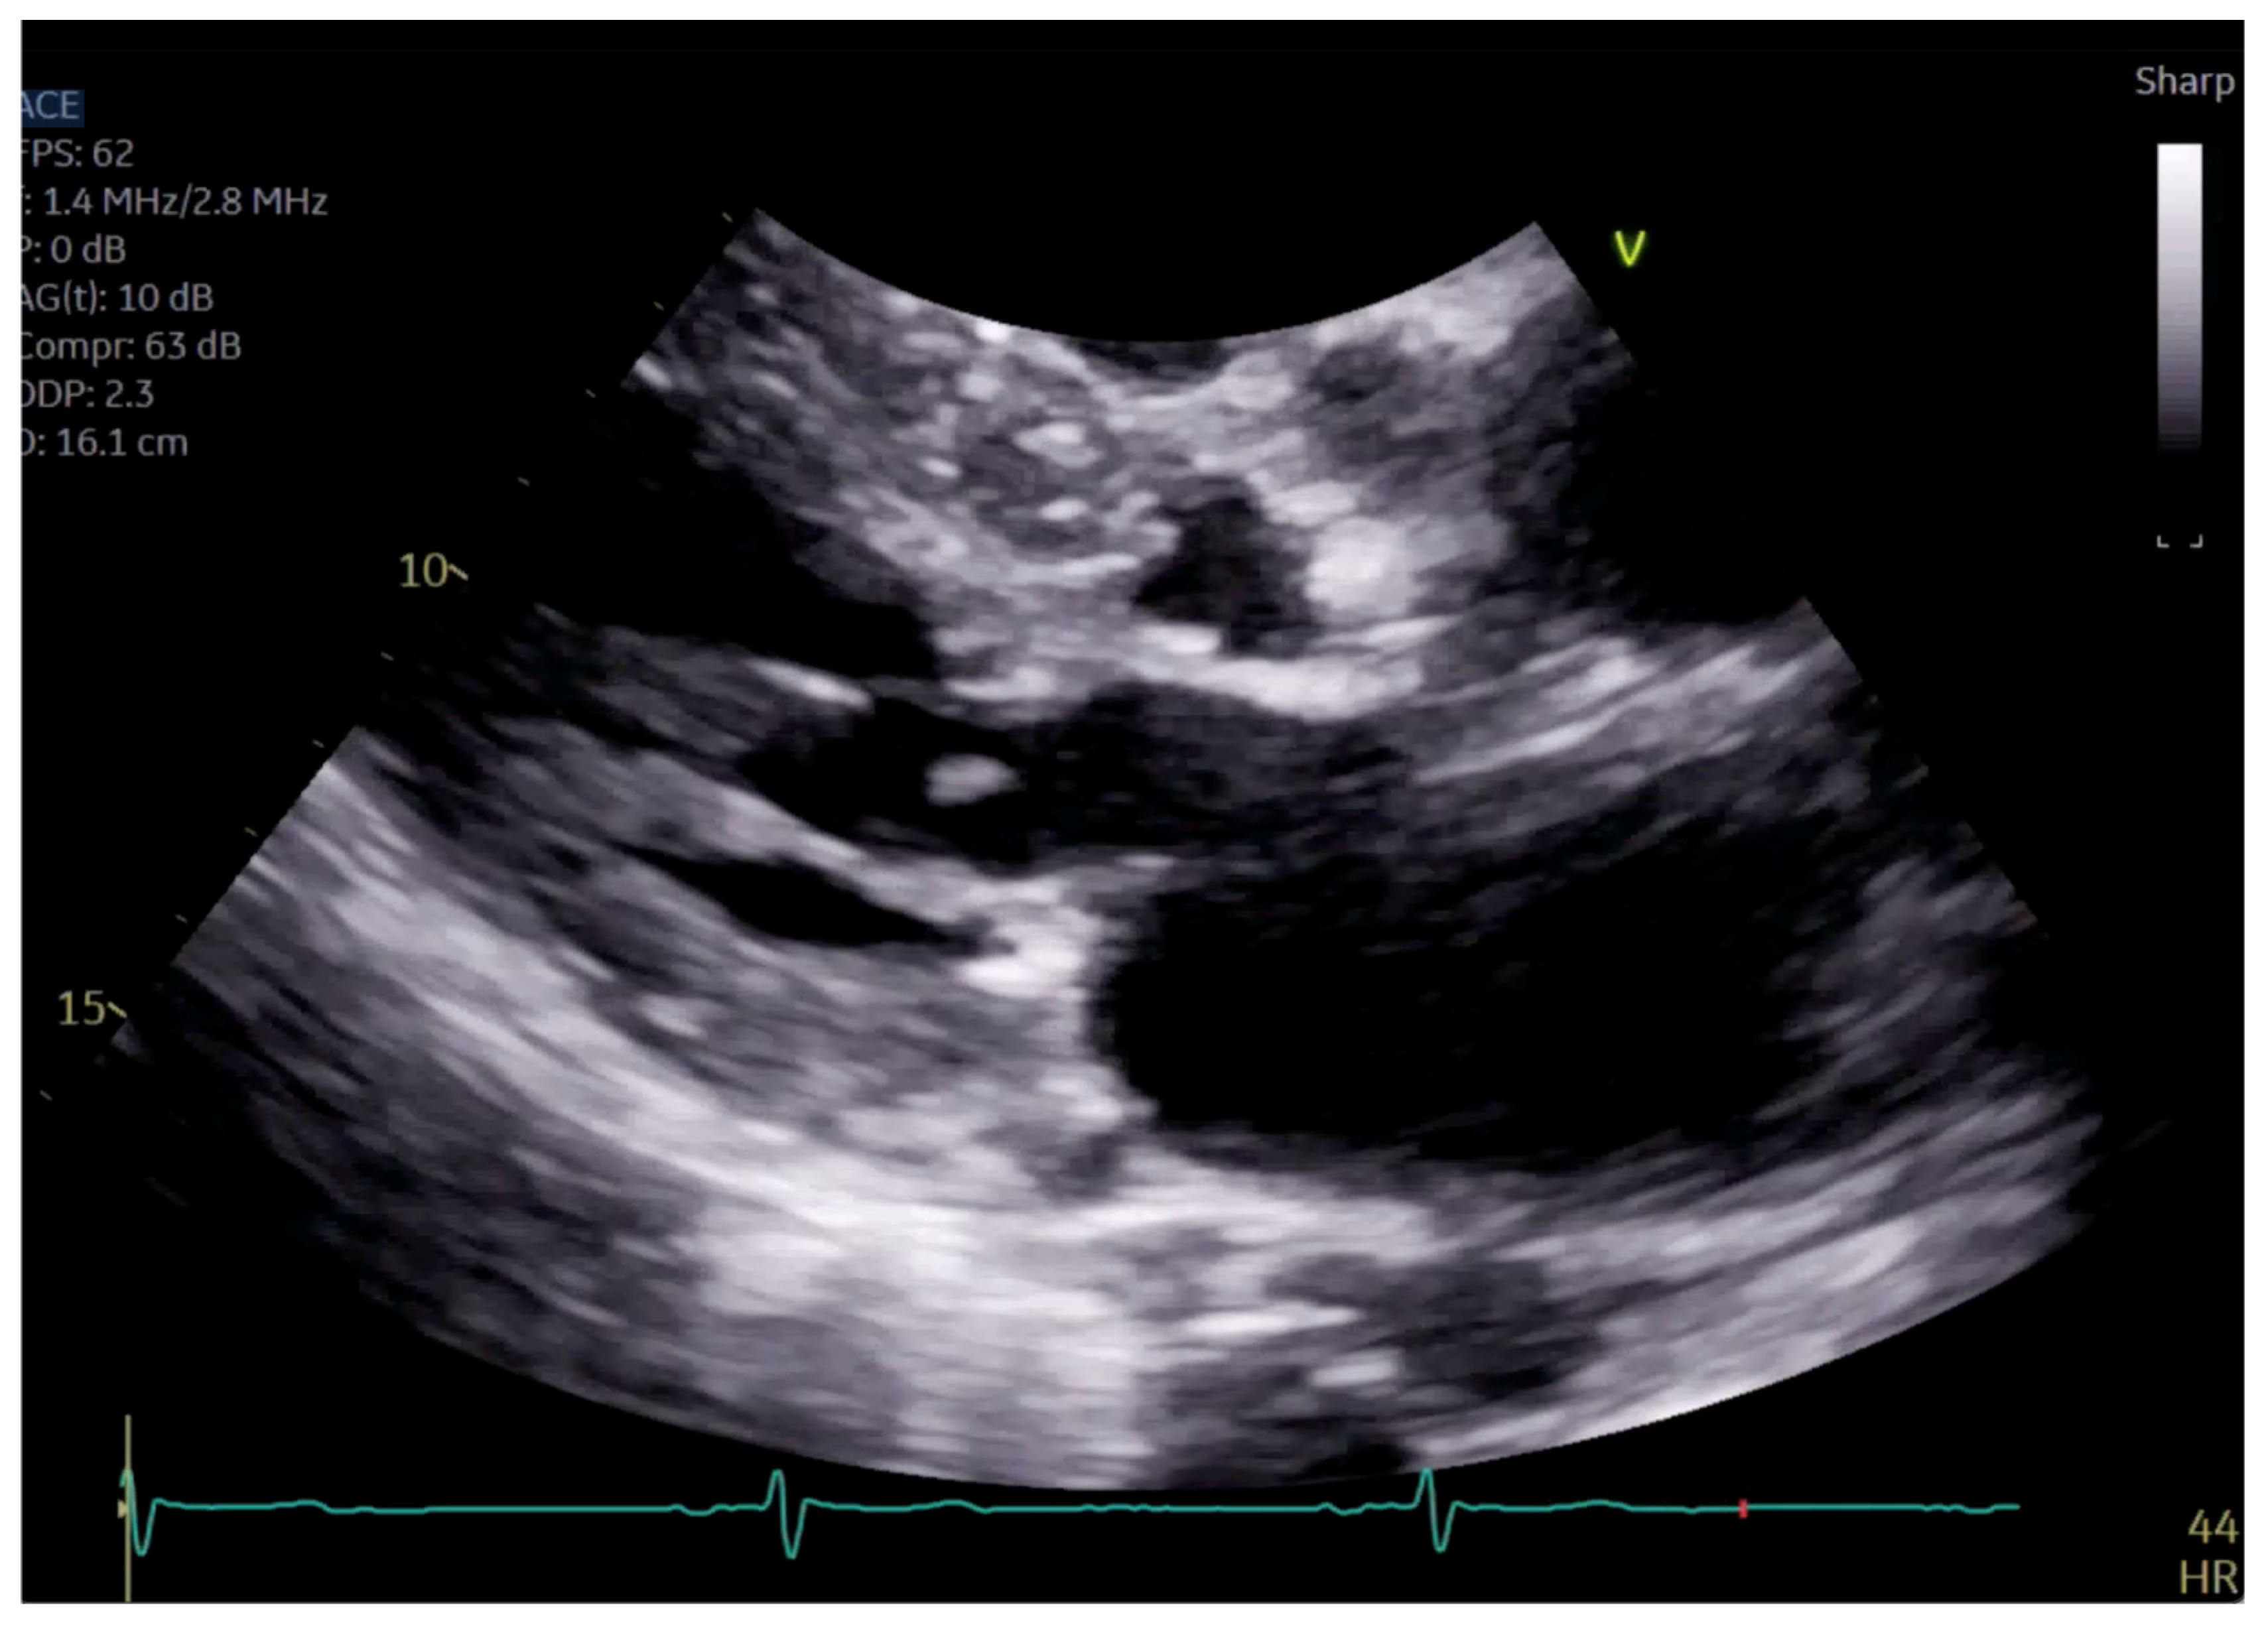

Figure 4.

Close up of mitral valve on parasternal long axis view.

The patient had initial symptomatic improvement after the initiation of beta blockers but returned three months later with worsening dyspnea. Repeat TTE showed the resolution of SAM and LVOT obstruction, indicating that the initial SAM was related to dynamic LVOT obstruction, flow acceleration and Venturi forces related to the hyperdynamic state. However, there was persistent posterior MR despite the resolution of SAM, indicating a SAM-independent cause of primary MR that may have been missed on transthoracic imaging (Figure 4 and Figure 5, Supplementary Videos S2 and S3). Additionally, there was new right ventricular enlargement and an elevated pulmonary artery systolic pressure of 74 mmHg.